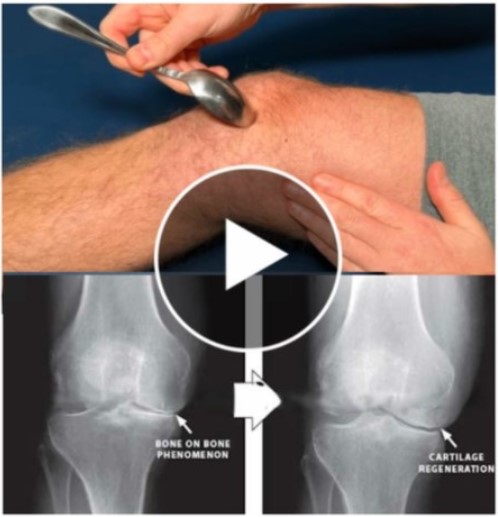

Top osteo-doctor, Dr. Hugo Rodier just released a 7-second joint-repair

hack that gives fast bone-on-bone relief.

“My knee cartilage re-developed and is fully back and strong. My doctor was

pleased to show me the [ before and after ] pics!”